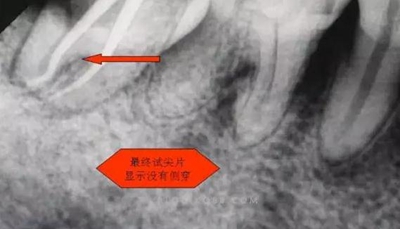

圖二

開髓后,發(fā)現(xiàn)是C型根管。

6.本病例,由于連接近遠中2個根管的融合區(qū)頰舌徑過于狹窄,在x線片上顯示不清,而唯一能表現(xiàn)的是近遠中分離的2個獨立的根管,將K銼放置到頰側根管內,有時在x線片上表現(xiàn)出根分叉處可能穿孔,這也是C型根管在x線上的重要特征。